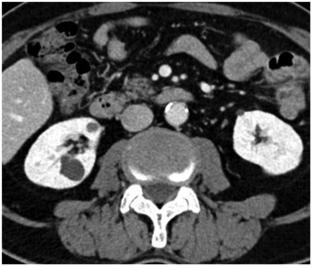

我们报告一例60多岁的ROS1融合阳性肺腺癌患者在克唑替尼治疗期间肾脏和肝脏出现多发性囊性病变。患者表现为发热、腹痛和少尿。增强CT显示肾脏和肝脏出现新的囊性病变,部分显示壁厚、间隔和高密度内容物。MRI显示t2加权图像信号强度不均,t1加权图像信号强度高低混合。部分囊肿沿囊肿壁呈T2低信号区和T1高信号区,扩散限制主要在肿块周围。经皮对囊肿进行引流,细胞学检查显示细胞数量增加,包括中性粒细胞。但未检出恶性细胞或微生物。基于这些影像学表现和实验室结果,患者被诊断为与克唑替尼相关的肾和肝囊肿。停用克唑替尼后症状改善,随访影像显示囊肿消退。这是第一份描述克里唑替尼相关肝囊肿MRI表现的报告。特征性MRI表现,如沿囊肿壁T2低/T1高,扩散限制主要在肿块周围,提示出血性成分,可能有助于区分克唑替尼相关囊肿与其他病变,包括转移和脓肿。

We report a case of a man in his 60s with ROS1 fusion-positive lung adenocarcinoma who developed multiple cystic lesions in both the kidneys and liver during crizotinib treatment. The patient presented with fever, abdominal pain, and oliguria. Contrast-enhanced CT revealed new cystic lesions in both the kidneys and liver, with some showing thick walls, septa, and hyperdense contents. MRI demonstrated heterogeneous signal intensities on T2-weighted images and mixed low to high signal intensities on T1-weighted images. Some cysts displayed T2 hypointense and T1 hyperintense areas along the cyst walls, with diffusion restriction predominantly at the periphery of the masses. Percutaneous drainage of the cysts was performed, and cytology revealed an increase in the number of cells, including neutrophils. However, no malignant cells or microorganisms were detected. Based on these imaging findings and laboratory results, the patient was diagnosed with crizotinib-associated renal and hepatic cysts. Symptoms improved after crizotinib discontinuation, and follow-up imaging showed cyst regression. This is the first report describing MRI findings for crizotinib-associated hepatic cysts. Characteristic MRI findings, such as T2 hypointensity/T1 hyperintensity along the cyst walls and diffusion restriction predominantly at the periphery of the masses, suggesting hemorrhagic components, may help differentiate crizotinib-associated cysts from other lesions, including metastases and abscesses.